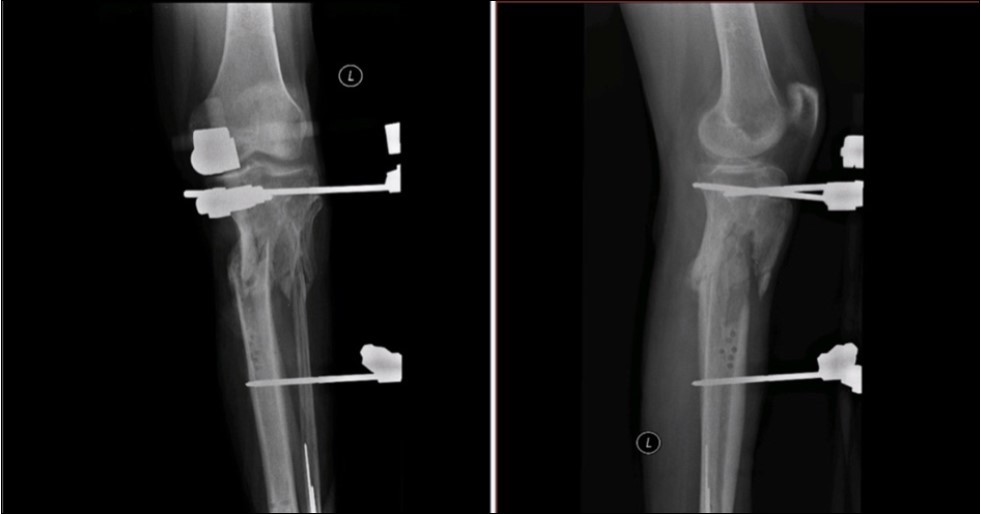

Case No.2 is about a man of 44 years old, where the injury caused by falling in ebrieta under the wheels of the bus. Primary acute treatment in the district hospital and then transferred to the Trauma Center of the Regional Hospital with open fracture of the tibia by Gustillo-Anderson IIIB 11. Extensive decollement of soft calf tissues up to the knee. Other diagnoses included the fracture of malleoli lateralis, acute hemorrhagic shock, traumatic shock, crash syndrome, acute alcohol intoxication.

Revision of limb perfusion and pulsation of marginal vessels. There was no detected injury of marginal vessels and nerves. MESS Absolute indication of amputation <7

Revision of soft tissue - extensive contusolaceration of the lower limb from the Achilles tendon through the whole calf to the medial side of the thigh - circular detachment of the skin and subcutis from the fascia, macroscopic contamination.

Application of external fixation and Ki wires to stabilization of fragments.